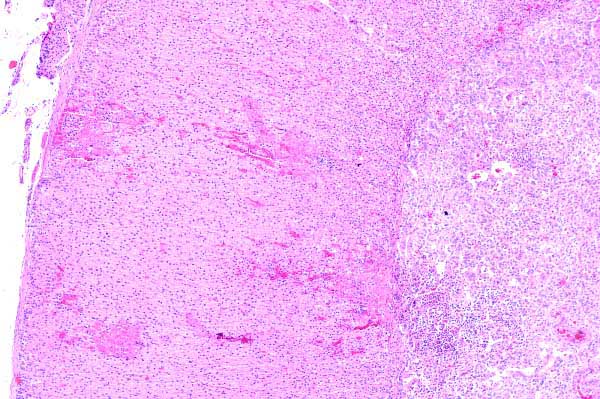

Within the cortex (C) and the medulla (M), there are small, intensely eosinophilic areas, often adjacent to a cellular infiltrate.